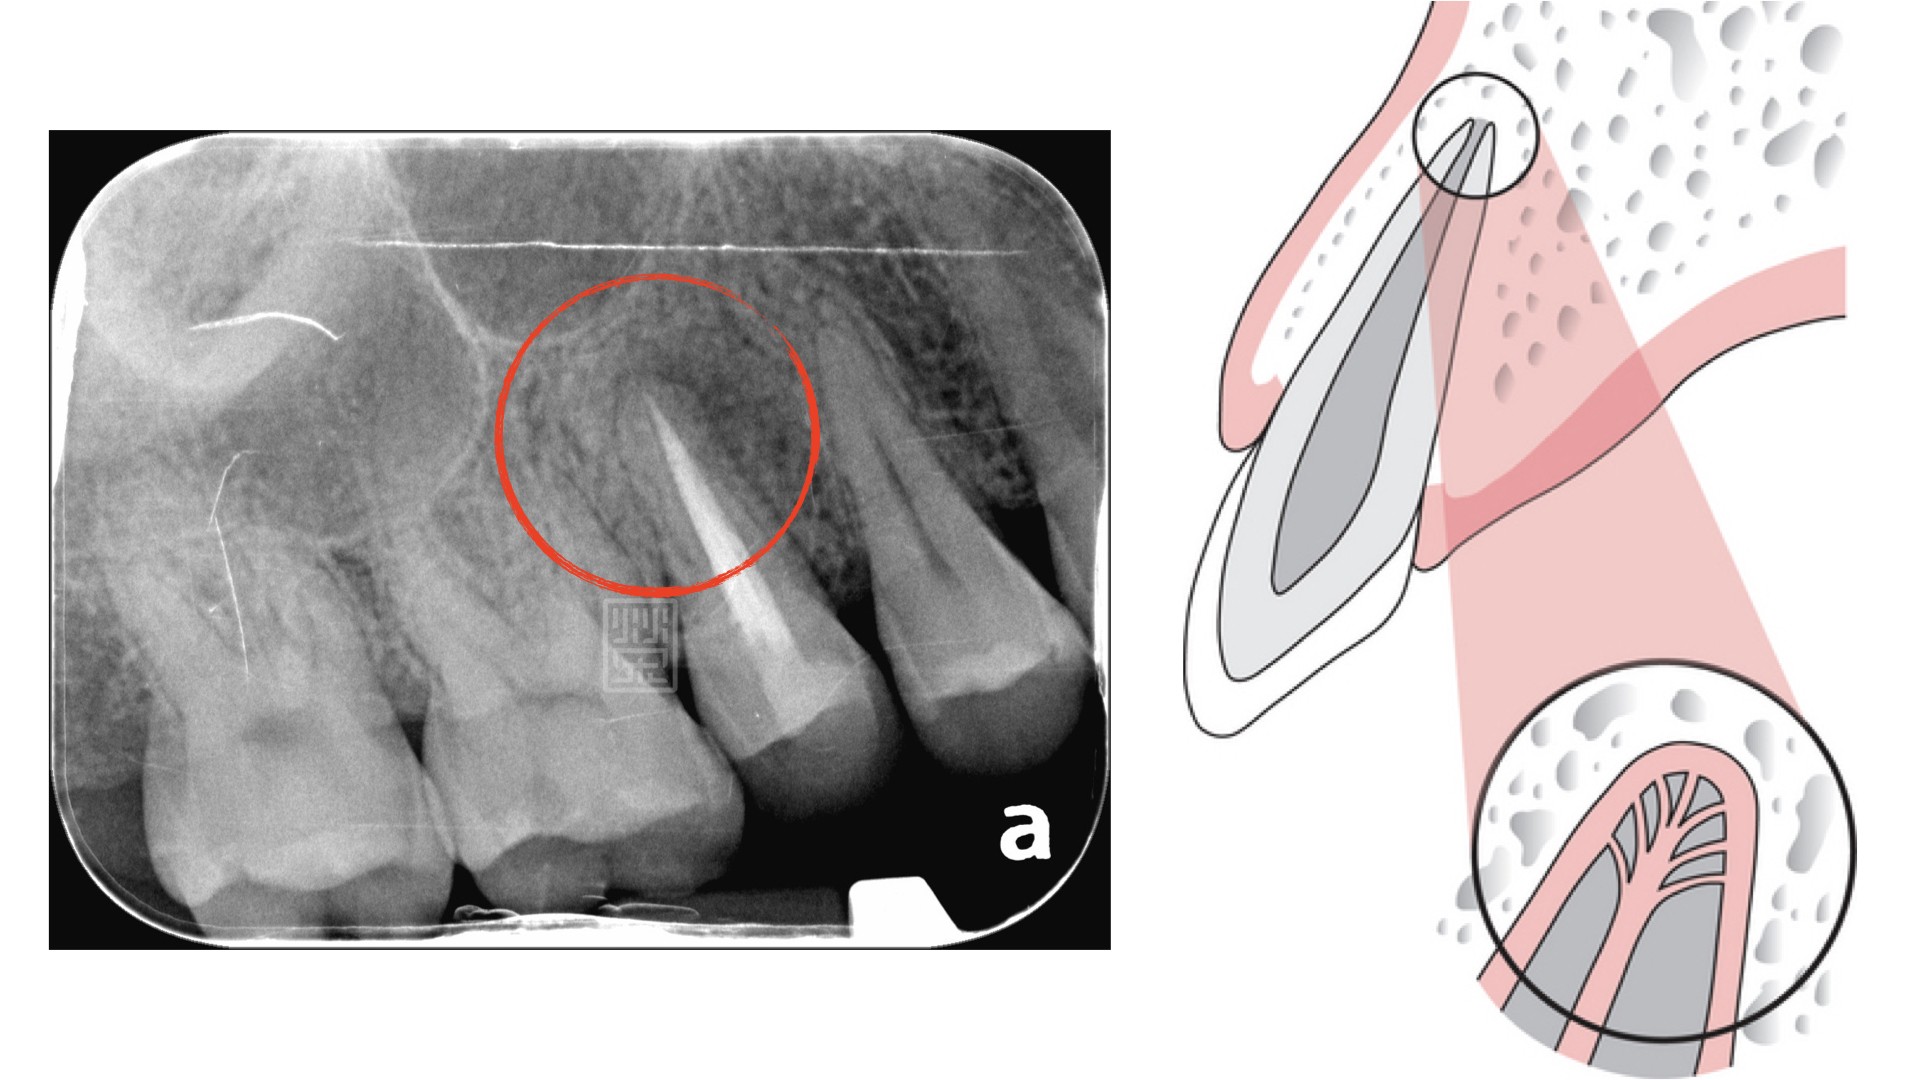

根尖處清潔完後兩個月,明顯可以看到根尖處骨頭修復,並且有牙周韌帶重新恢復的跡象。這是因為減少細菌後,減少牙根周圍的刺激,周圍組織就會恢復健康的狀態。從右邊卡通圖知道,牙根尖並不是只有一條神經管,而是有多個分支,根管治療時,將主要的管腔清創,其餘的就需要消毒藥水與超音波器械將管腔內的殘餘組織清除。

為什麼差一點點,就會有這麼大的影響呢?因為牙髓腔中原本是由牙髓組織填滿,但是並不是一條水管的構造,比較像是樹枝分布,特別是在牙根尖5毫米處,如果有未清創或是未封填的區域,長期下來細菌滋生,等到細菌數增加,就會傷害牙根周圍組織,進而造成腫脹與疼痛。

為什麼差一點點,就會有這麼大的影響呢?因為牙髓腔中原本是由牙髓組織填滿,但是並不是一條水管的構造,比較像是樹枝分布,特別是在牙根尖5毫米處,如果有未清創或是未封填的區域,長期下來細菌滋生,等到細菌數增加,就會傷害牙根周圍組織,進而造成腫脹與疼痛。